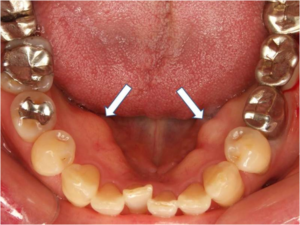

下顎隆起とは、下顎骨の小臼歯付近の骨表面が限局的に盛り上がり、デコボコとした硬いこぶのようになっている状態です。

口を開けて下顎の内側を観察した際に、硬いふくらみが左右両方、もしくは片側だけにある場合、下顎隆起が疑われます。